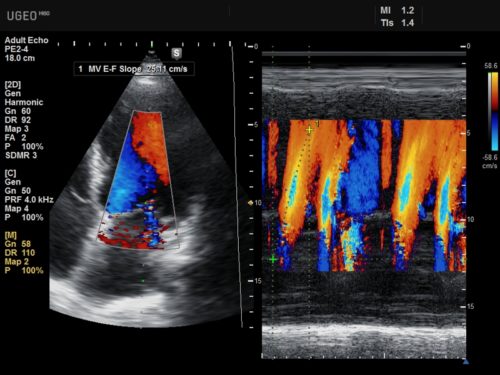

При цветовой допплерографии используется метод наложения – на двумерную картинку сердца/сосуда накладывают множество контрольных микро объемов. На экране в реальном режиме времени оказываются отображенными потоки крови, распределенные в пространстве, с указанием их скорости и направления. Каждая точка отображаемой картинки, окрашивается в определенный цвет.

Цветовой М-режим

Метод позволяет получать в М-режиме (цветовое допплеровское картирование) визуальную картинку оболочек и стенок сердца, сжатие и расслабление клапанов. Изображение дается в реальном режиме времени с цветовым кодированием движения крови. На сегодня эта методика – одна из самых популярных среди всех вариантов эхокардиографии.